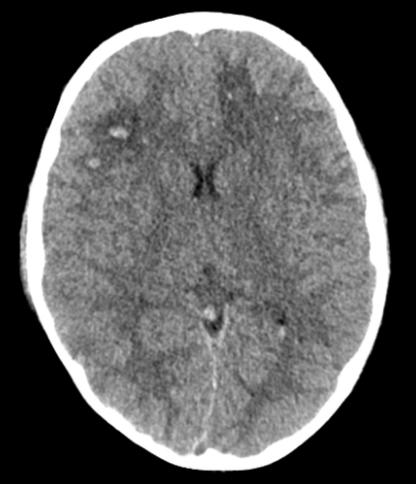

腦挫傷 - DAI

• 瀰漫性軸索損傷 (Diffuse axonal injury, DAI)

• 突然的加速、減速或旋轉力量導致腦組織剪切傷

• 造成許多小血管微出血

• 進一步導致腦皮質實質組織瘀傷